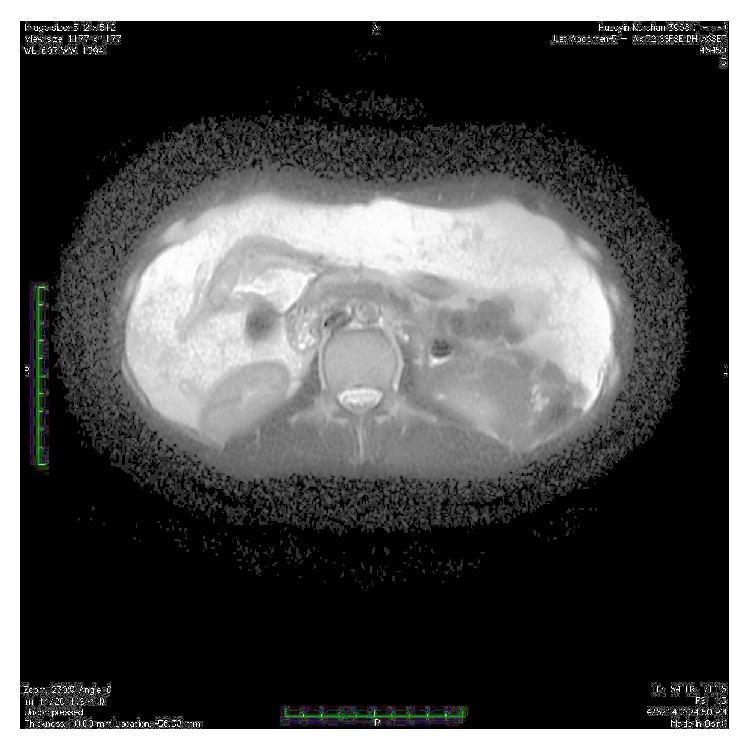

Although lipomas are encapsulated benign tumors, systemic lipomatosis defines infiltrative nonencapsulated tumors resembling normal adipose tissue. Abdominal lipomatosis and intestinal lipomatosis are different clinicopathological entities with similar clinical symptoms. We describe here a case presenting with upper gastrointestinal bleeding from eroded submucosal lipoma at duodenum secondary to intestinal lipomatosis and abdominal lipomatosis.

虽然脂肪瘤是有包膜的良性肿瘤,但系统性脂肪过多症定义的是类似正常脂肪组织的浸润性无包膜肿瘤。腹部脂肪过多症和肠道脂肪过多症是具有相似临床症状的不同临床病理实体。我们在此描述一例因肠道脂肪过多症和腹部脂肪过多症继发十二指肠黏膜下脂肪瘤糜烂导致上消化道出血的病例。